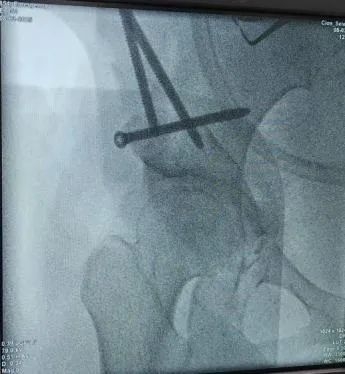

图5-6:术中截骨

图7:术后影像(髋臼对股骨头的包容良好)该手术的实施标志着我院保髋医疗技术在骨科领域的重大突破、填补了区域技术空白,为更多髋关节发育不良患者提供了新的治疗选择。